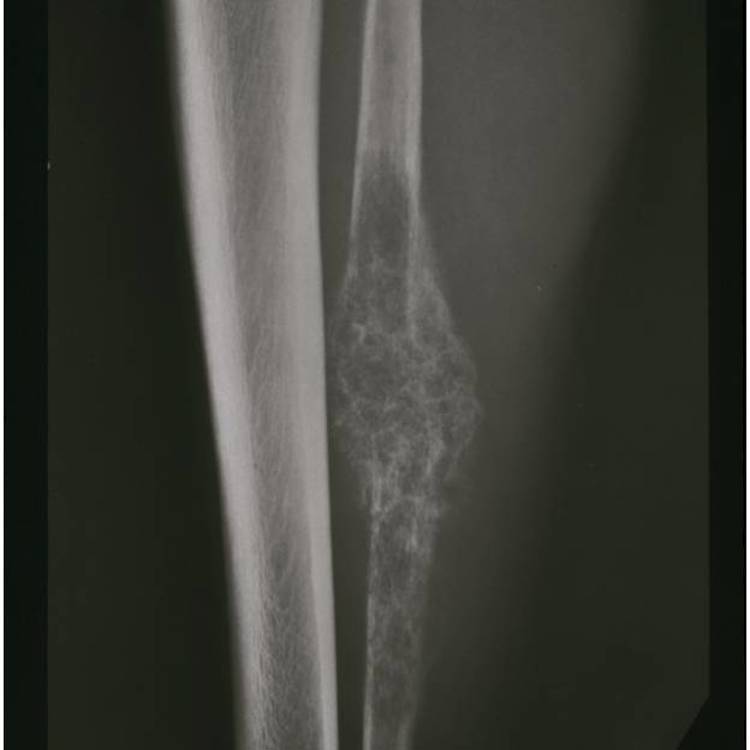

Radiographic imaging is used to help form a diagnosis. These include X-Ray, MRI, CT and Bone Scans

An example of an Mesenchymal Chondrosarcoma MRI is shown.